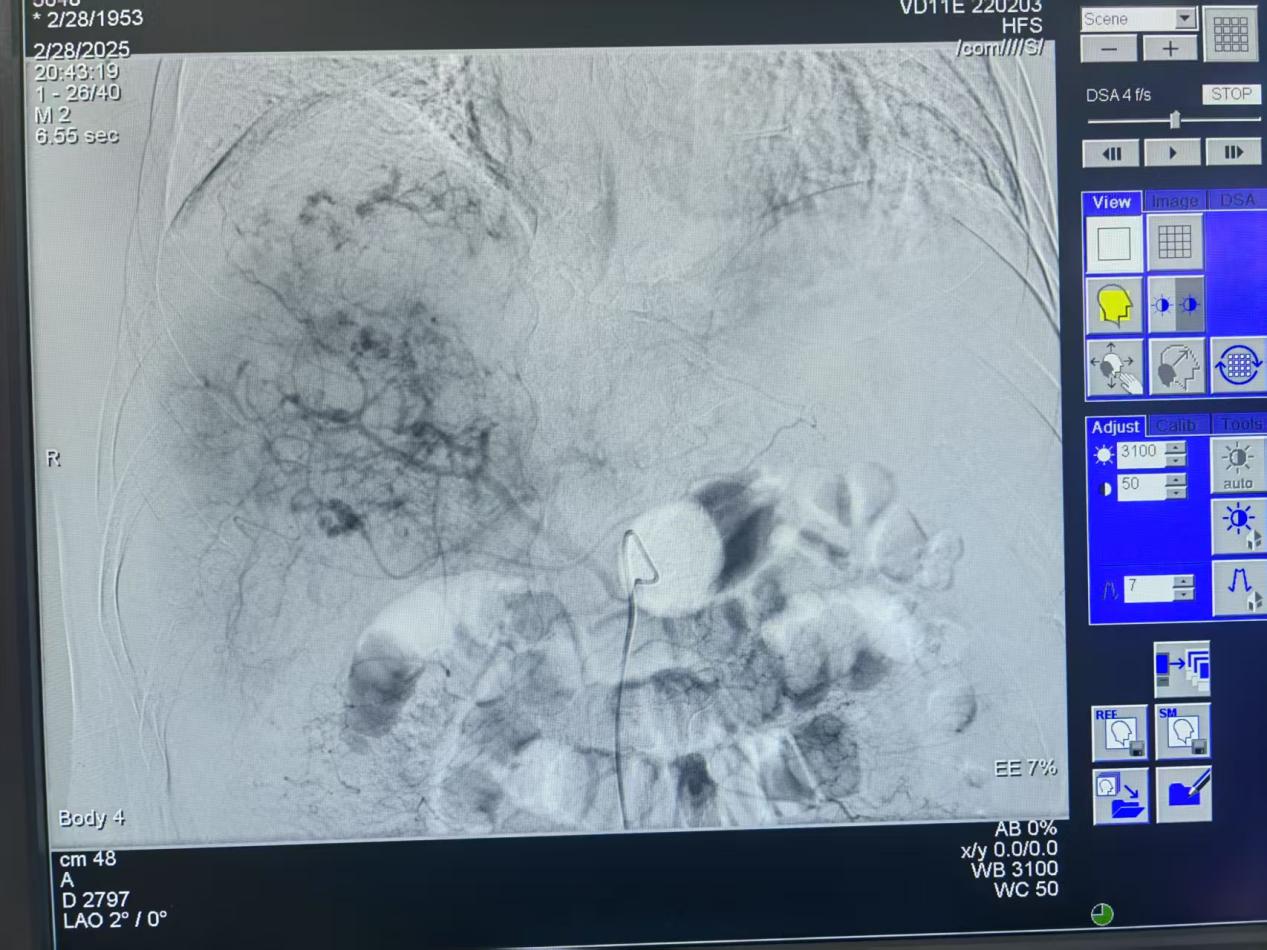

術(shù)前患者肝臟血管造影圖片

圖片8.jpg

術(shù)后患者肝臟血管造影圖片